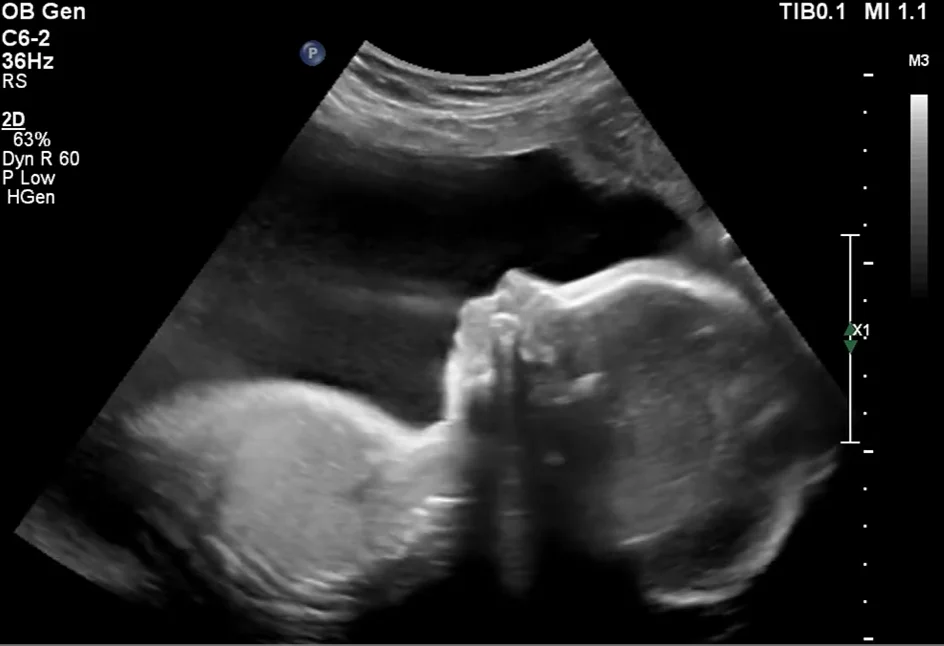

Sứt môi hở hàm ếch ở thai nhi (Cleft lip and palate)

• Sứt môi hở hàm ếch ở thai nhi (Cleft lip and palate)